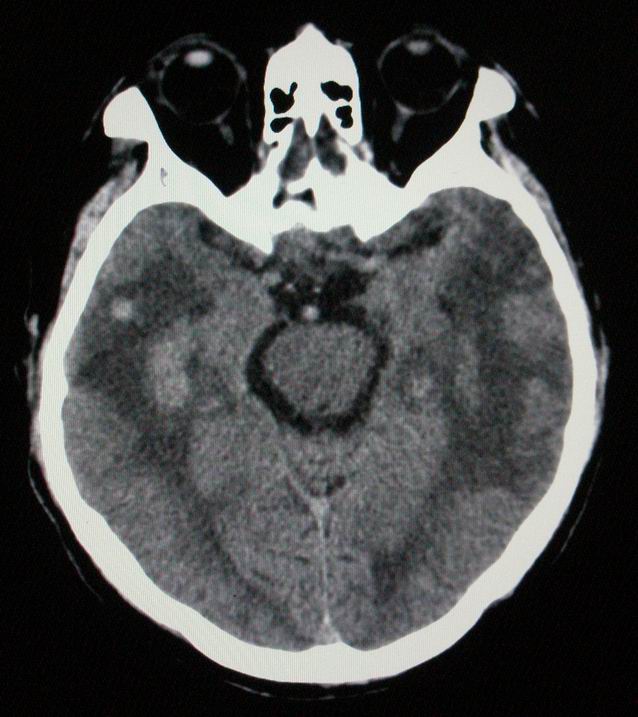

以下是引用随光逐影在2008-4-5 7:46:00的发言:[br]1)考虑为:多发性脑转移瘤。建议:行进一步检查。2)多发性腔隙性脑梗塞。3)脑白质病。4)脑萎缩。

以下是引用zjzjr在2008-4-5 9:00:00的发言:[br]1.双侧颞叶占位性病变,考虑为转移瘤可能性大。[br]2.左侧基底节区陈旧性腔隙性脑梗塞。[br]3.脑白质病。建议mri进一步检查。

以下是引用xuhuihong在2008-4-5 0:59:00的发言:[br]1.双侧颞叶占位性病变,考虑为转移瘤可能性大。[br]2.左侧基底节区陈旧性腔隙性脑梗塞。[br]3.脑白质病。建议mri进一步检查。

以下是引用形影不离在2008-4-4 23:29:00的发言:[br]1.双侧颞叶占位性病变,考虑为转移瘤可能性大。[br]2.左侧基底节区陈旧性腔隙性脑梗塞。[br]3.脑白质病。